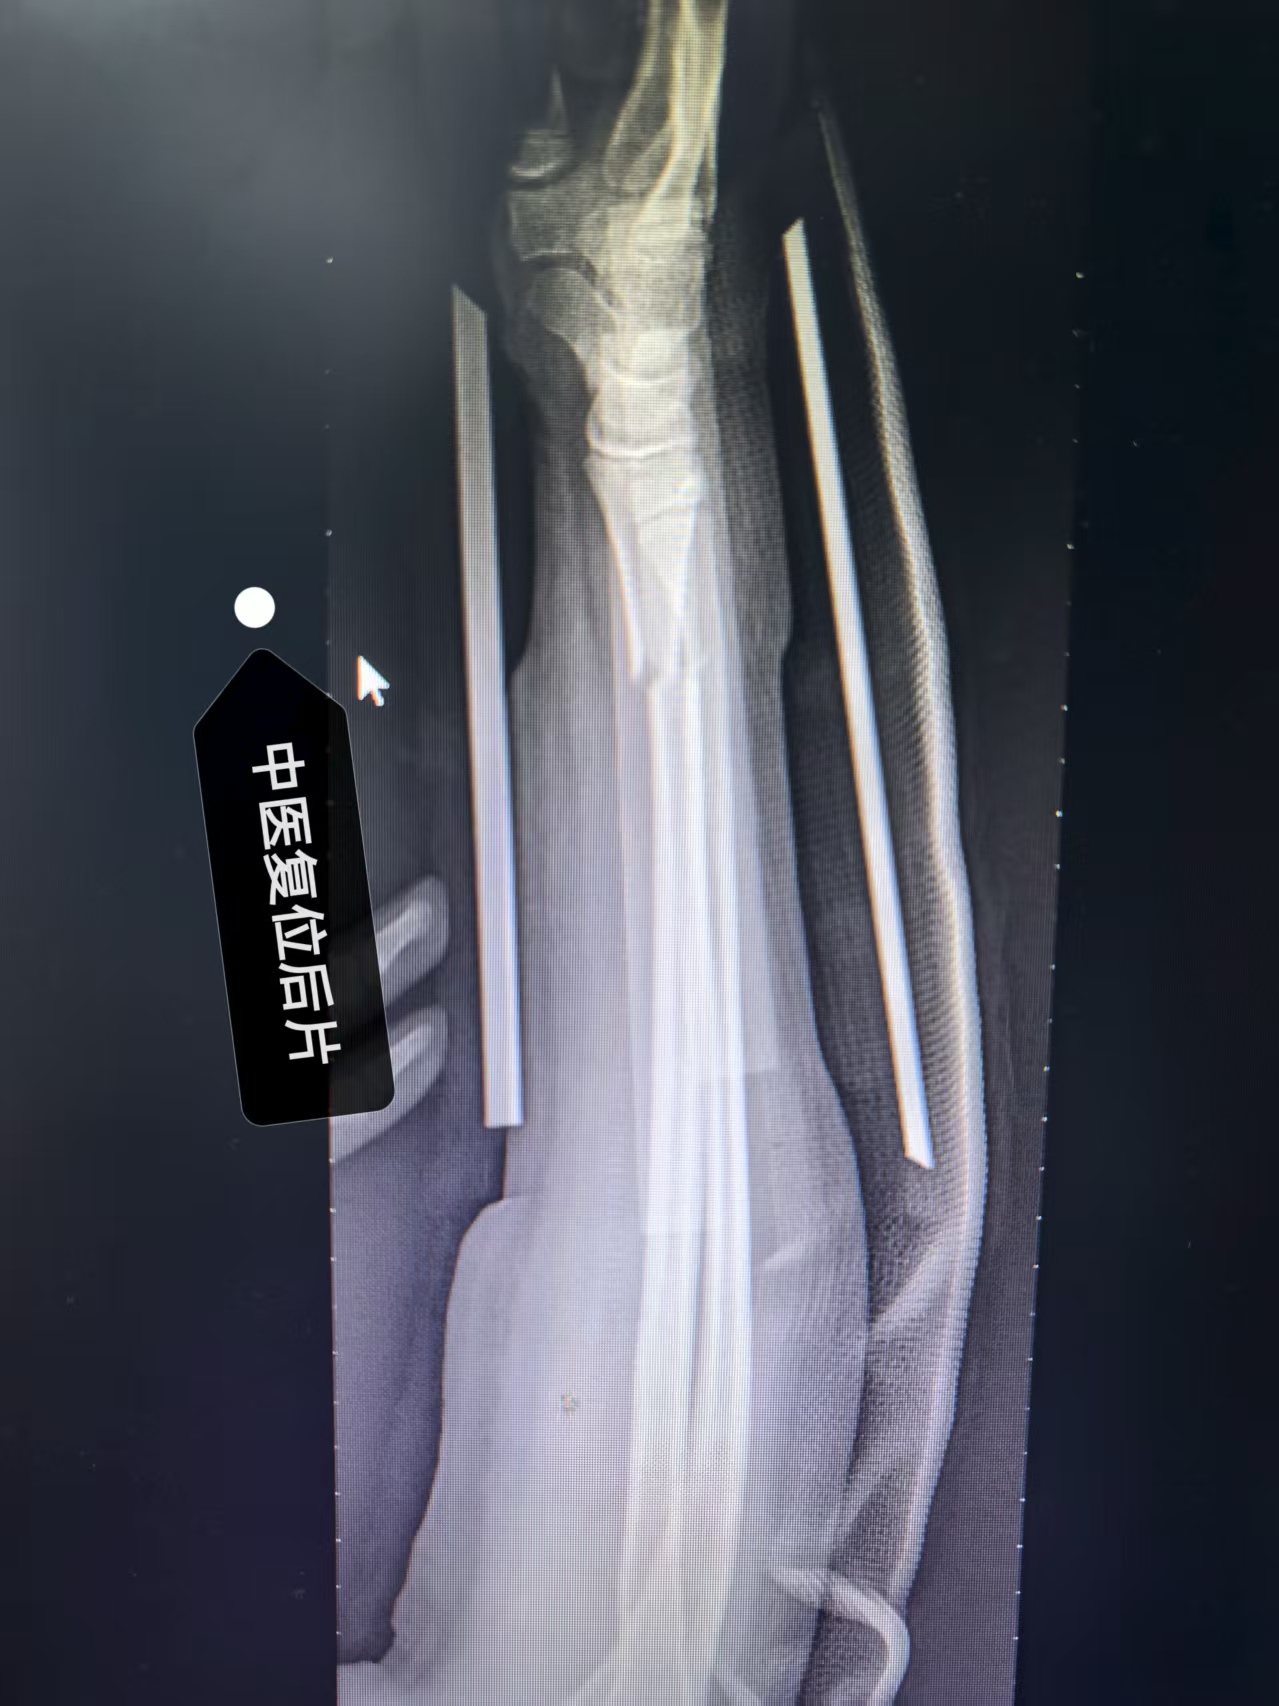

(以上二图,是复位固定三月后复诊的照片,疗效非常满意,骨折基本解剖复位愈合,患儿前臂功能恢复如初,旋转功能良好)